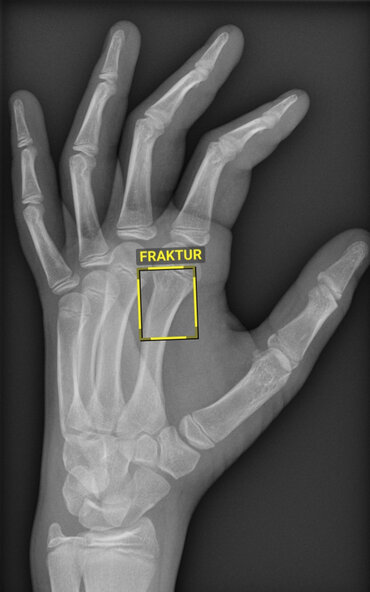

Das System erkennt selbst feinste oder überlagerte Knochenbrüche und kennzeichnet sie mit einem Rahmen. Gerade einmal 90 Sekunden benötigt es dafür. Zur weiteren Analyse und finalen Diagnose wird den Mediziner*innen im Anschluss das vollständige Röntgenbild mit den Markierungen der KI auf den Bildschirm gespielt. „Die Künstliche Intelligenz kann den*die Radiolog*in dabei niemals ersetzen und arbeitet auch nicht besser als der Mensch. Sie ist wie ein zweites Paar Augen, das den Ärzt*innen assistiert, oder wie ein Kopilot, der zur Unterstützung mit im Cockpit sitzt. Die Verantwortung für eine korrekte Diagnose obliegt dabei weiterhin den Ärzt*innen“, sagt Prof. Dr. Ali Seif, Direktor des Instituts für Klinische und Interventionelle Radiologie.

Anwendung findet die neue Technik zunächst in der Unfallchirurgie zur Diagnostik von Knochenfrakturen. Weitere Schritte sind an der UMG allerdings bereits in Vorbereitung: So steht die Systemeinführung für Röntgenaufnahmen der Lunge bereits unmittelbar bevor. Später soll die KI auch in der Bildgebung für den gesamten Thorax, also den Brustkorbbereich, eingesetzt werden.